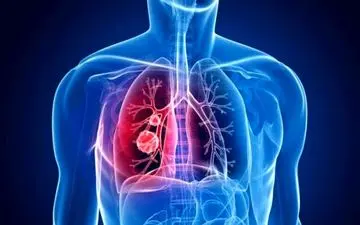

با همه گیری کووید ۱۹ در جهان، تشخیص ابتلا به سرطان ریه و یا ویروس کرونا به یک چالش برای کادر درمانی تبدیل شده است.

فوق تخصص ریه گفت: بیماری که دچار سرفه، بدن درد، ضعف، تب، اختلال بویایی و چشایی شده است، به احتمال زیاد به کرونا مبتلا…